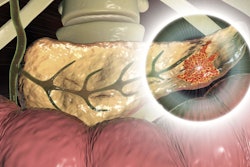

In their study, the researchers sought to develop an AI tool that can assist clinicians in identifying patients at high risk for pancreatic cancer, an aggressive cancer that is often undetected until later stages and has a relatively poor prognosis, according to co-first author Davide Placido, a doctoral candidate at the University of Copenhagen.

As there are currently no reliable biomarkers or screening tools that can detect pancreatic cancer early, the group sought to develop an AI tool that could help clinicians identify high-risk patients. These patients could then be enrolled in prevention or surveillance programs and hopefully benefit from early treatment, according to Yuan.

Although it's difficult to exactly pinpoint the diagnosis patterns that predicted risk, the researchers uncovered significant associations with certain clinical characteristics and the higher risk of pancreatic cancer development. These included diagnoses of diabetes, pancreatic and biliary tract diseases, and gastric ulcers.